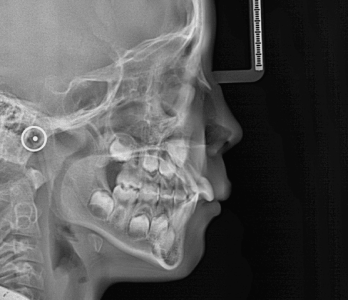

Radiografías 2D (alta resolución)

- Teleradiografía lateral

- Teleradiografía frontal

Estudios cefalométricos

- Ricketts

- McNamara

- Steiner

- Roth Jarabak

- Bjork Jarabak

- Sassouni +

- Quirúrgico (tejidos blandos)